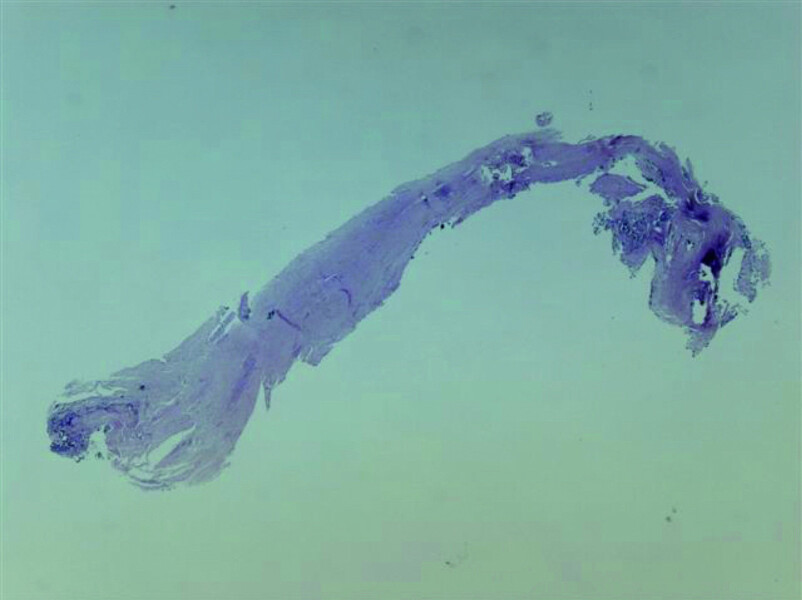

Fig. 20: Tissue removed from the endodontic space three months after transplantation (H&E stain; 2× magnification).

Fig. 21: Tissue removed from the endodontic space three months after transplantation (H&E stain; 4× magnification).